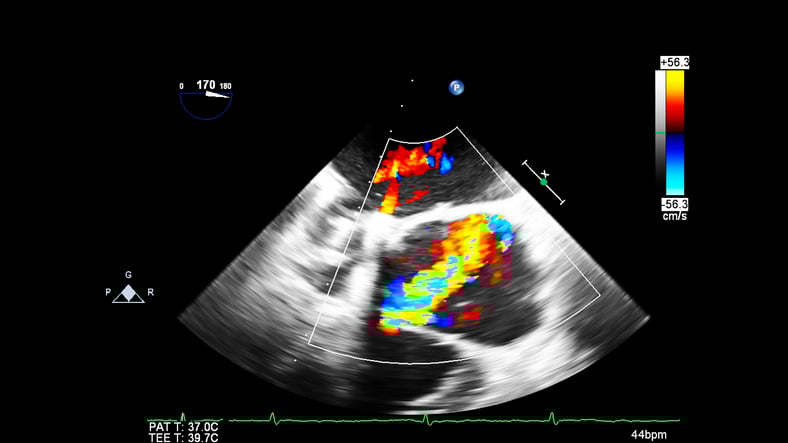

Point-of-care transesophageal echocardiography (TEE) is becoming more widely used in cardiac arrest. It has four main advantages over TTE: a reliable sonographic window, continuous imaging of the heart during resuscitation, elimination of pauses in chest compressions, and potential to detect abnormalities that are more difficult to visualize on TTE. [15] However, barriers exist to widespread implementation of TEE in the ED, namely access to training, the cost of purchasing, storing, and reprocessing equipment. More research highlighting the benefits of point-of-care TEE is needed, and access to equipment and training opportunities would be greatly beneficial to the emergency medicine community.